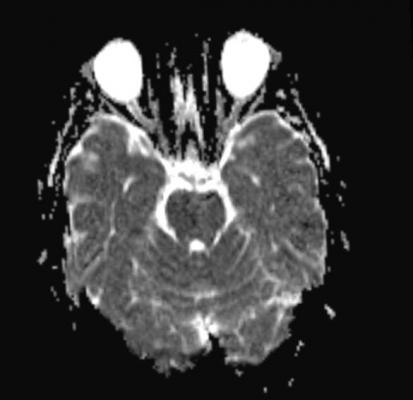

The MRIs measured the amount of damage to the brain’s white matter, which connects different brain regions, based on the movement of water molecules in the brain tissue. Seventeen players, or 43 percent, had levels of movement 2.5 standard deviations below those of healthy people of the same age, which is considered evidence of traumatic brain injury with a less than 1 percent error rate.

Twelve of the former athletes, or 30 percent, showed evidence on traditional MRI of injury to the brain due to disruption of the nerve axons, those parts of nerve cells that allow brain cells to transmit messages to each other. On the tests of thinking skills, about 50 percent had significant problems on executive function, 45 percent on learning or memory, 42 percent on attention and concentration, and 24 percent on spatial and perceptual function.